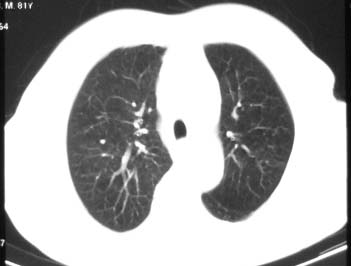

81 男 以头昏入院

两肺多发异常密度,其中双上肺病变主要为纤维增殖性改变;右中肺内侧段病变密度相对均匀,无恶性特征,周围可见卫星灶和浸润表现,邻近胸膜稍增厚,所见纵隔层面无肿大淋巴结和胸腔积液。提示结核性改变。如果可能建议强化。

两肺多发异常密度,其中双上肺病变主要为纤维增殖性改变;右中肺内侧段病变密度相对均匀,无恶性特征,周围可见卫星灶和浸润表现,邻近胸膜稍增厚,所见纵隔层面无肿大淋巴结和胸腔积液。提示结核性改变.

符合多叶多段多形态的特点.